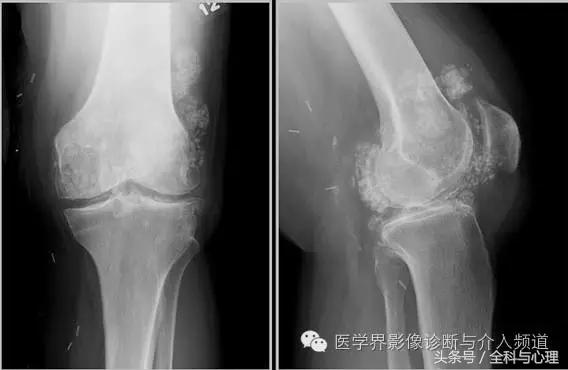

4、痛风石

为尿酸盐沉积形成,发生在关节周围软组织、包括韧带、肌腱、滑囊,眼、耳、鼻、喉、皮肤, 50%的钙化为X线平片可见。

痛风石,可见软组织肿胀及钙化灶。